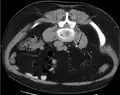

Calcium-containing stones are relatively radiodense (opaque to X-rays), and they can often be detected by a traditional radiography of the abdomen that includes the kidneys, ureters, and bladder (KUB film).[59] KUB radiography, although useful in monitoring size of stone or passage of stone in stone formers, might not be useful in the acute setting due to low sensitivity.[60] Some 60% of all renal stones are radiopaque.[61][62] In general, calcium phosphate stones have the greatest density, followed by calcium oxalate and magnesium ammonium phosphate stones. Cystine calculi are only faintly radiodense, while uric acid stones are usually entirely radiolucent.[63]

Bilateral kidney stones can be seen on this KUB radiograph. There are phleboliths in the pelvis, which can be misinterpreted as bladder stones.